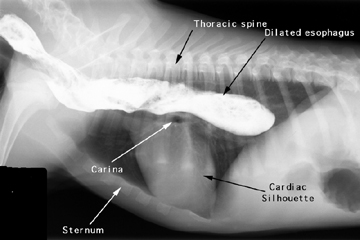

For an esophagram, the patient is given a barium paste or liquid suspension to evaluate esophageal motility, mucosal irregularites and size.